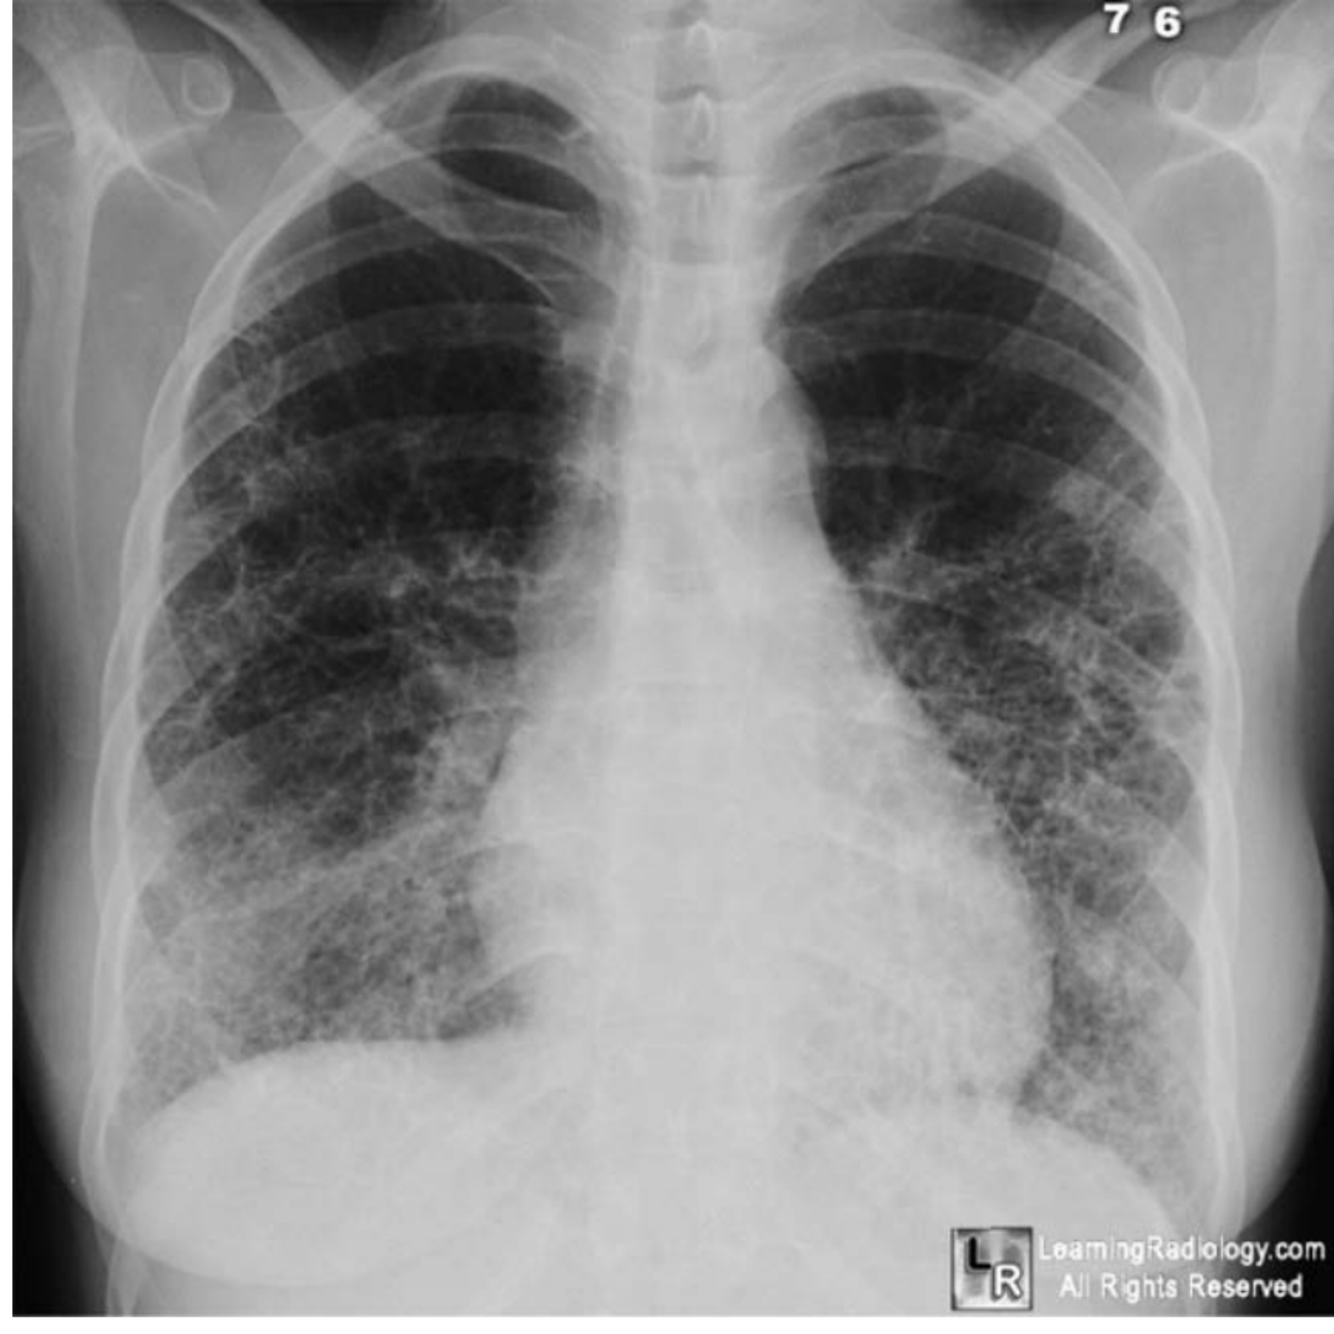

cXR

CXR reveals evidence of his previous surgery and signs within his

existing lung.

It demonstrates marked volume loss of the left hemithorax with shift of

the mediastinum and elevation of the hemidiaphragm. Also the pleura is

calcified.